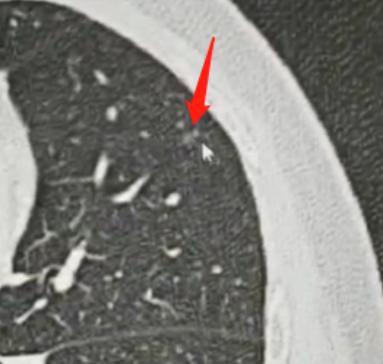

昨天接诊了个23岁的小伙子,一进诊室眼眶就通红,坐下没两句话就带着哭腔问我:“乔医生,我是不是快不行了?您说实话,我还剩几个月时间?” 这话一出来,我就知道他肯定是被检查结果吓懵了。 我先示意他别慌:“先稳住情绪,别自己吓自己,把你的片子给我看看,咱们慢慢说。” 接过他手里的检查报告和影像片,我仔细逐帧翻看,这才发现他肺里长了十几枚磨玻璃结节,难怪小伙子会这么害怕,换谁查出这么多结节,心里都得打鼓。 反复确认片子细节,又对照了他之前几次的复查记录后,我抬头肯定地跟他说:“你这情况一点危险都没有,踏踏实实过好日子就行,完全不影响寿命。” 小伙子愣了一下,显然没敢相信这话。 我接着跟他解释,这里面最大的那枚结节,考虑是原位癌性质,但他几次复查下来,结节都没有任何变化,这说明它基本不生长,恶性程度也几乎可以忽略不计。 对于这种多发的磨玻璃结节,咱们宁愿耐心观察随访,也不能盲目做手术乱切,毕竟手术对身体伤害太大,反而得不偿失。 我跟他说,我这儿有不少和他情况一样的病人,都是多发磨玻璃结节,跟着我随访了十几年、二十年,结节一直没变化,照样正常工作、结婚生子,过着和普通人一样的生活。我让他半年过来复查一次,有我盯着,绝对不会耽误病情。 我特意叮嘱他,别因为这些密度淡的小结节打乱自己的生活,该上学上学、该工作工作,不用整天揪着这事焦虑。真要是哪次复查发现某个结节有细微变化,咱们再针对性处理,到时候治疗效果和现在手术是一样的,根本不危及生命。 听我说完这些,小伙子紧绷的肩膀终于松了下来...... 其实想跟有多发肺结节的朋友们说一句,遇到这种情况别慌也别害怕。结节不等于癌症,没变化就安心观察,有问题咱们就及时处理。日子都是一步步过的,不用被未知的恐惧困住,慢慢走,总能顺利通关。[玫瑰][作揖]